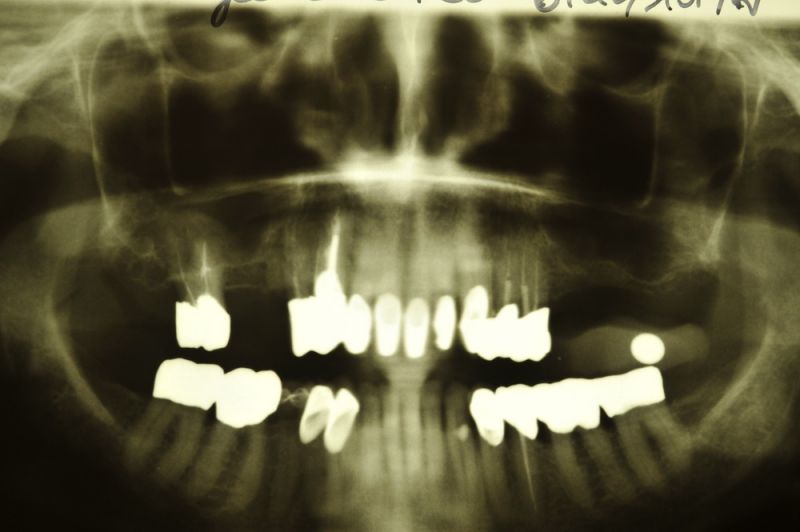

Aus parodontalen Gründen mussten bei der Patientin im Oberkieferseitenzahnbereich mehrere Zähne entfernt werden. Auf der rechten Seite wurden bereits zwei Implantate, mit einem externen Sinuslift verbunden, gesetzt.

Heute wurden die Zähne 15 und 17 entfernt. An Zahn 15 erkennt man ein großes Granulom, im Sinne einer chronischen Entzündung, um die Wurzelspitze herum. Dieses Granulom hat der Patientin keinerlei Beschwerden verursacht. Der Zahn hätte aber so nicht gehalten oder versorgt werden können, weil dieses Granulom die Tendenz hat sich weiter zu vergrößern und dabei Knochen einzuschmelzen, der wiederum für den Halt der Zähne benötigt wird.

In aller Regel sind diese Zähne sehr lange Zeit vollkommen beschwerdefrei und erst im Rahmen röntgenologischer Untersuchungen werden derartige Befunde offenbar.